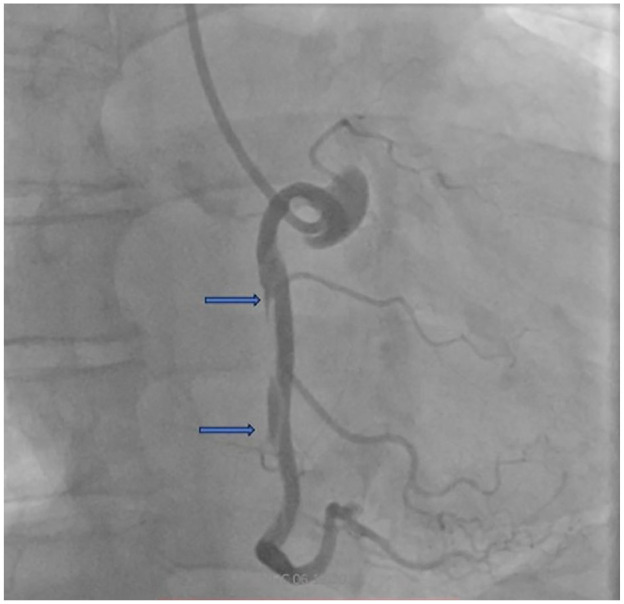

In this paper, we present 2 patients with ST-elevation myocardial infarction in the course of Spontaneous Coronary Artery Dissection. The first patient, a female admitted with STEMI, was diagnosed with SCAD with intravascular imaging and treated with IVUS-guided PCI. In the second patient, a young male hospitalized due to angina and STEMI, SCAD was not identified initially, and the patient was treated conservatively. Based on these cases, we show different faces of the same disease that imply different diagnostics and management strategies. We draw attention to the fact that the disease affects not only young women without atherosclerotic risk factors and that it is not always possible to avoid generally not recommended invasive treatment and anticoagulant therapy. The paper also discusses the disease's pathophysiology and its diagnosis methods.

本文报告2例自发性冠状动脉剥离过程中st段抬高型心肌梗死。第一位患者是一名入院的STEMI女性患者,通过血管内成像诊断为SCAD,并接受ivus引导的PCI治疗。第二例患者为年轻男性,因心绞痛和STEMI住院,最初未发现SCAD,患者接受保守治疗。基于这些病例,我们展示了同一疾病的不同面貌,意味着不同的诊断和管理策略。我们提请注意的事实是,这种疾病不仅影响没有动脉粥样硬化危险因素的年轻女性,而且通常不推荐的侵入性治疗和抗凝治疗并不总是可以避免的。本文还讨论了该病的病理生理及诊断方法。